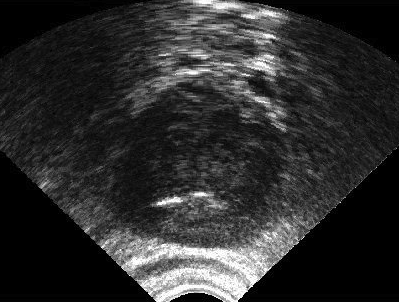

We generated 500 images from their corresponding gold-standard images. Furthermore, we generated 20 different segments for each image, assuming that there were 20 users. Figure 4 shows three examples of real and synthetic TRUS images. One should bear in mind that the purpose here was not to simulate the images realistically, but rather to have a base from which to generate variable segments from a perfect segment. Figure 5 shows an example of the gold segments and simulated user contours. The variability, coupled with the gold segment, is what is needed to validate our approach.

Sample images are depicted in Figure 6 (top row). Generally, one assumes that prostate segmentation is a relatively easy task. However, the variability of such segmentation remains considerable, and this is conspicuous in Figure 6 (bottom row).